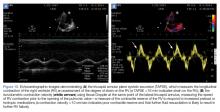

Figure 10.

The longitudinal contraction of the RV can be easily measured on bedside ultrasound. In the apical view, M-mode imaging through the lateral annulus of the tricuspid valve will provide a measurement of the systolic movement of the RV. Increased strain on the RV will lead to decreased tricuspid annular plane systolic excursion ( Figure 10a ).38

From the same apical view, tissue Doppler at the lateral tricuspid annulus will give a tricuspid annular peak velocity, a measure of the isovolumetric contraction velocity. This measurement will provide a measure of the contractile reserve of the RV (Figure 10b). A measure of less than 10 cm/sec indicates that further volume and inotropic challenges to the RV will not be effective, and the focus should be to decrease RV afterload with pulmonary vasodilators. 34,39,40